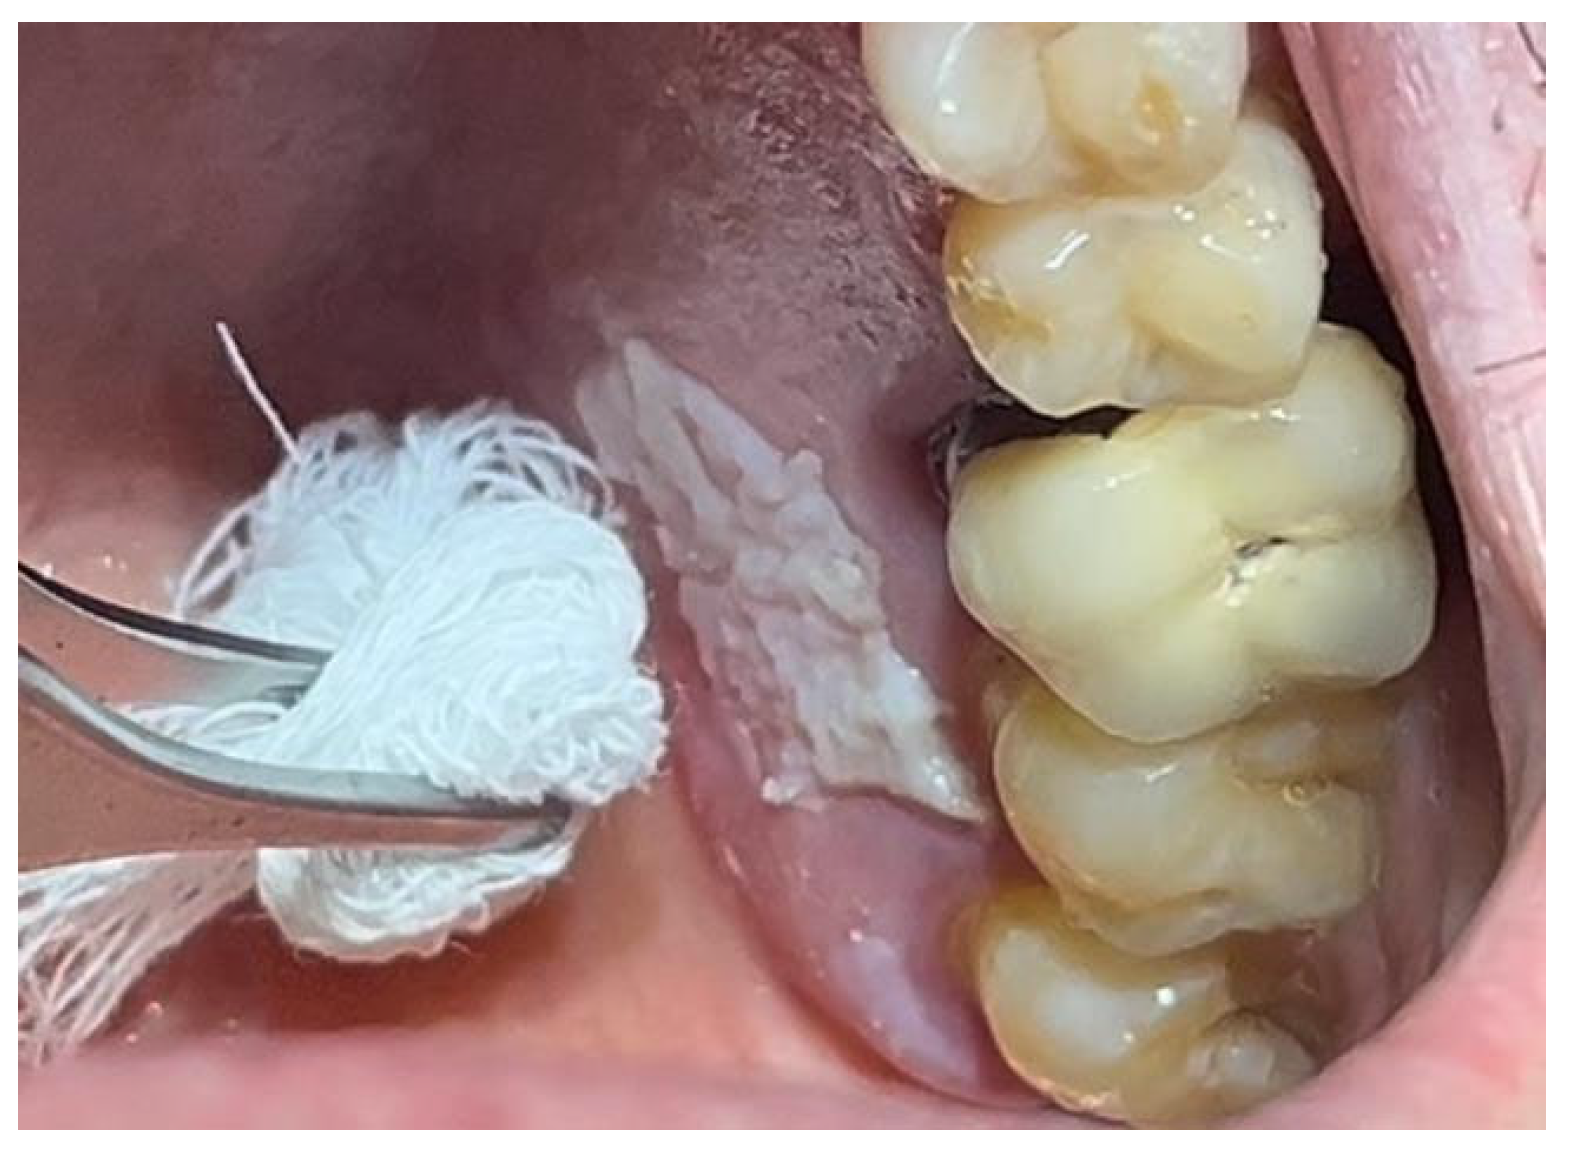

A similar technique was used in a 45-year-old patient with controlled hypertension, treated for the extraction of tooth 1.6 (Figure 11) and subsequent post-extraction implant-prosthetic rehabilitation (Figure 12). The surgical site was treated with bone graft material (Bio-Oss®—Geistlich), and a small amount of Glubran II was applied (Figure 13). Once again, Glubran II proved to be highly effective in stabilizing the graft material at the surgical site, providing excellent hemostasis and strong mechanical resistance from the film formed after polymerization (Figure 14).

One week after surgery, no signs of inflammation or suppuration were observed at the site. New tissue formation was noted within the rehabilitated site (Figure 15). The patient reported no discomfort related to Glubran II use, and bleeding was controlled during the surgery, thus reducing the risks associated with the patient’s hypertensive condition.

Figure 13. Stabilization of synthetic bone material at the surgical site, undergoing implant-prosthetic rehabilitation with Glubran II using an endodontic needle.

Materials 18 02642 g013

Figure 14. Surgical site after the complete polymerization of Glubran II.

Materials 18 02642 g014